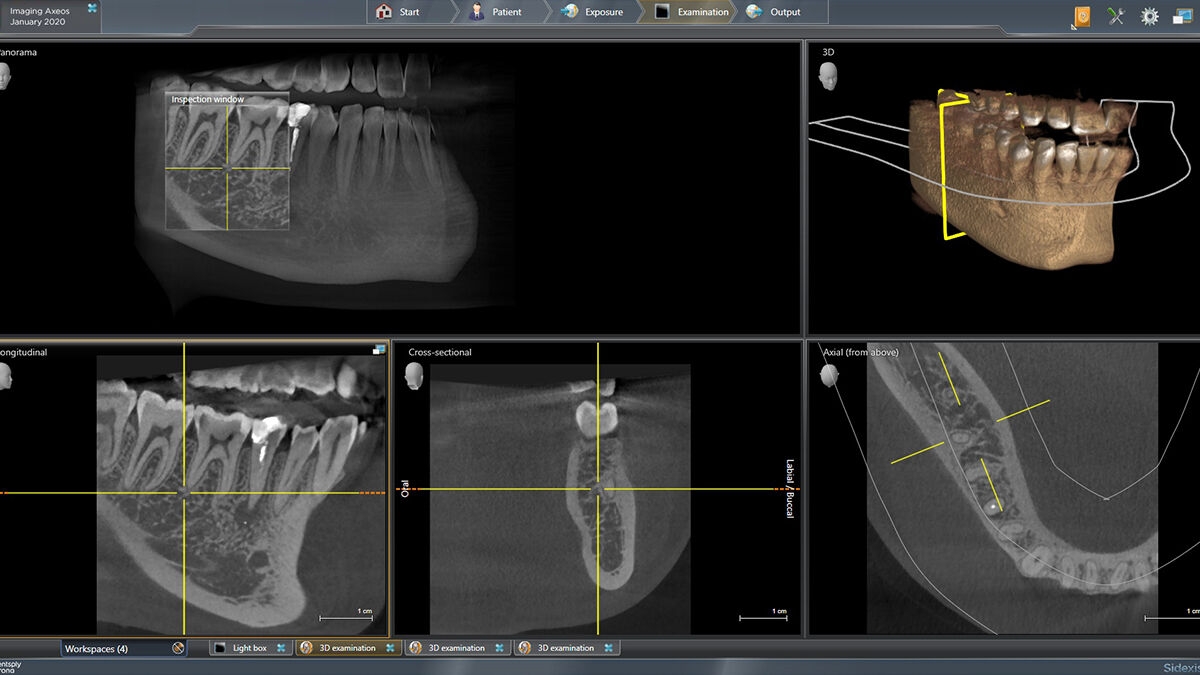

Exemplary 3D Images

Volume Ø 5 cm x 5.5 cm HD